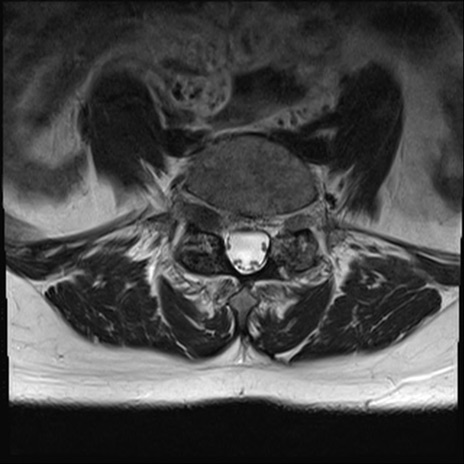

【整形】TIPS症例4 腰椎MRI T2WI(横断像)

横断像と矢状断像